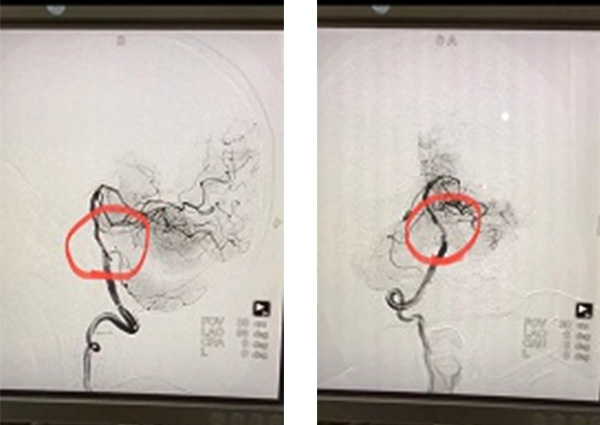

从死神手中夺生命,是马明辉医生日复一日的工作。急性脑血管病的治疗,关乎患者后续的生存质量,他不敢有丝毫怠慢,立即协助患者办理了住院,认真进行查体,结合CT结果,考虑患者可能存在严重血管病变,遂迅速完善相关血管因素检查和评估。DSA全脑血管造影提示:基底动脉起始段严重狭窄 ;左侧颈内动脉C5、C6轻度狭窄 ;左侧椎动脉显影不佳(非优势侧)—病根终于找到了。

患者病情复杂,多次论证,制定严密手术方案,在患者病情稳定后的第二周,马明辉医生为患者进行了全麻下经皮基底动脉狭窄处血管成形术及支架置入术。实际上,手术的风险远比想象的大,马医生和他的同事们顶着巨大的压力,仅用时1.5个小时就成功将血管打通。术后患者苏醒,自诉症状得到了明显改善,复查头部CT:无出血转化;血常规、肾功能未见异常。术后第二天,解除压迫器后,患者就已经完全恢复正常了。家属连声致谢:“马医生医术真是太精湛了,我爸症状明显减轻了,而且住院这几天医生护士就像亲人一样照顾他,我为五院点赞。”

术前DSA

术后DSA